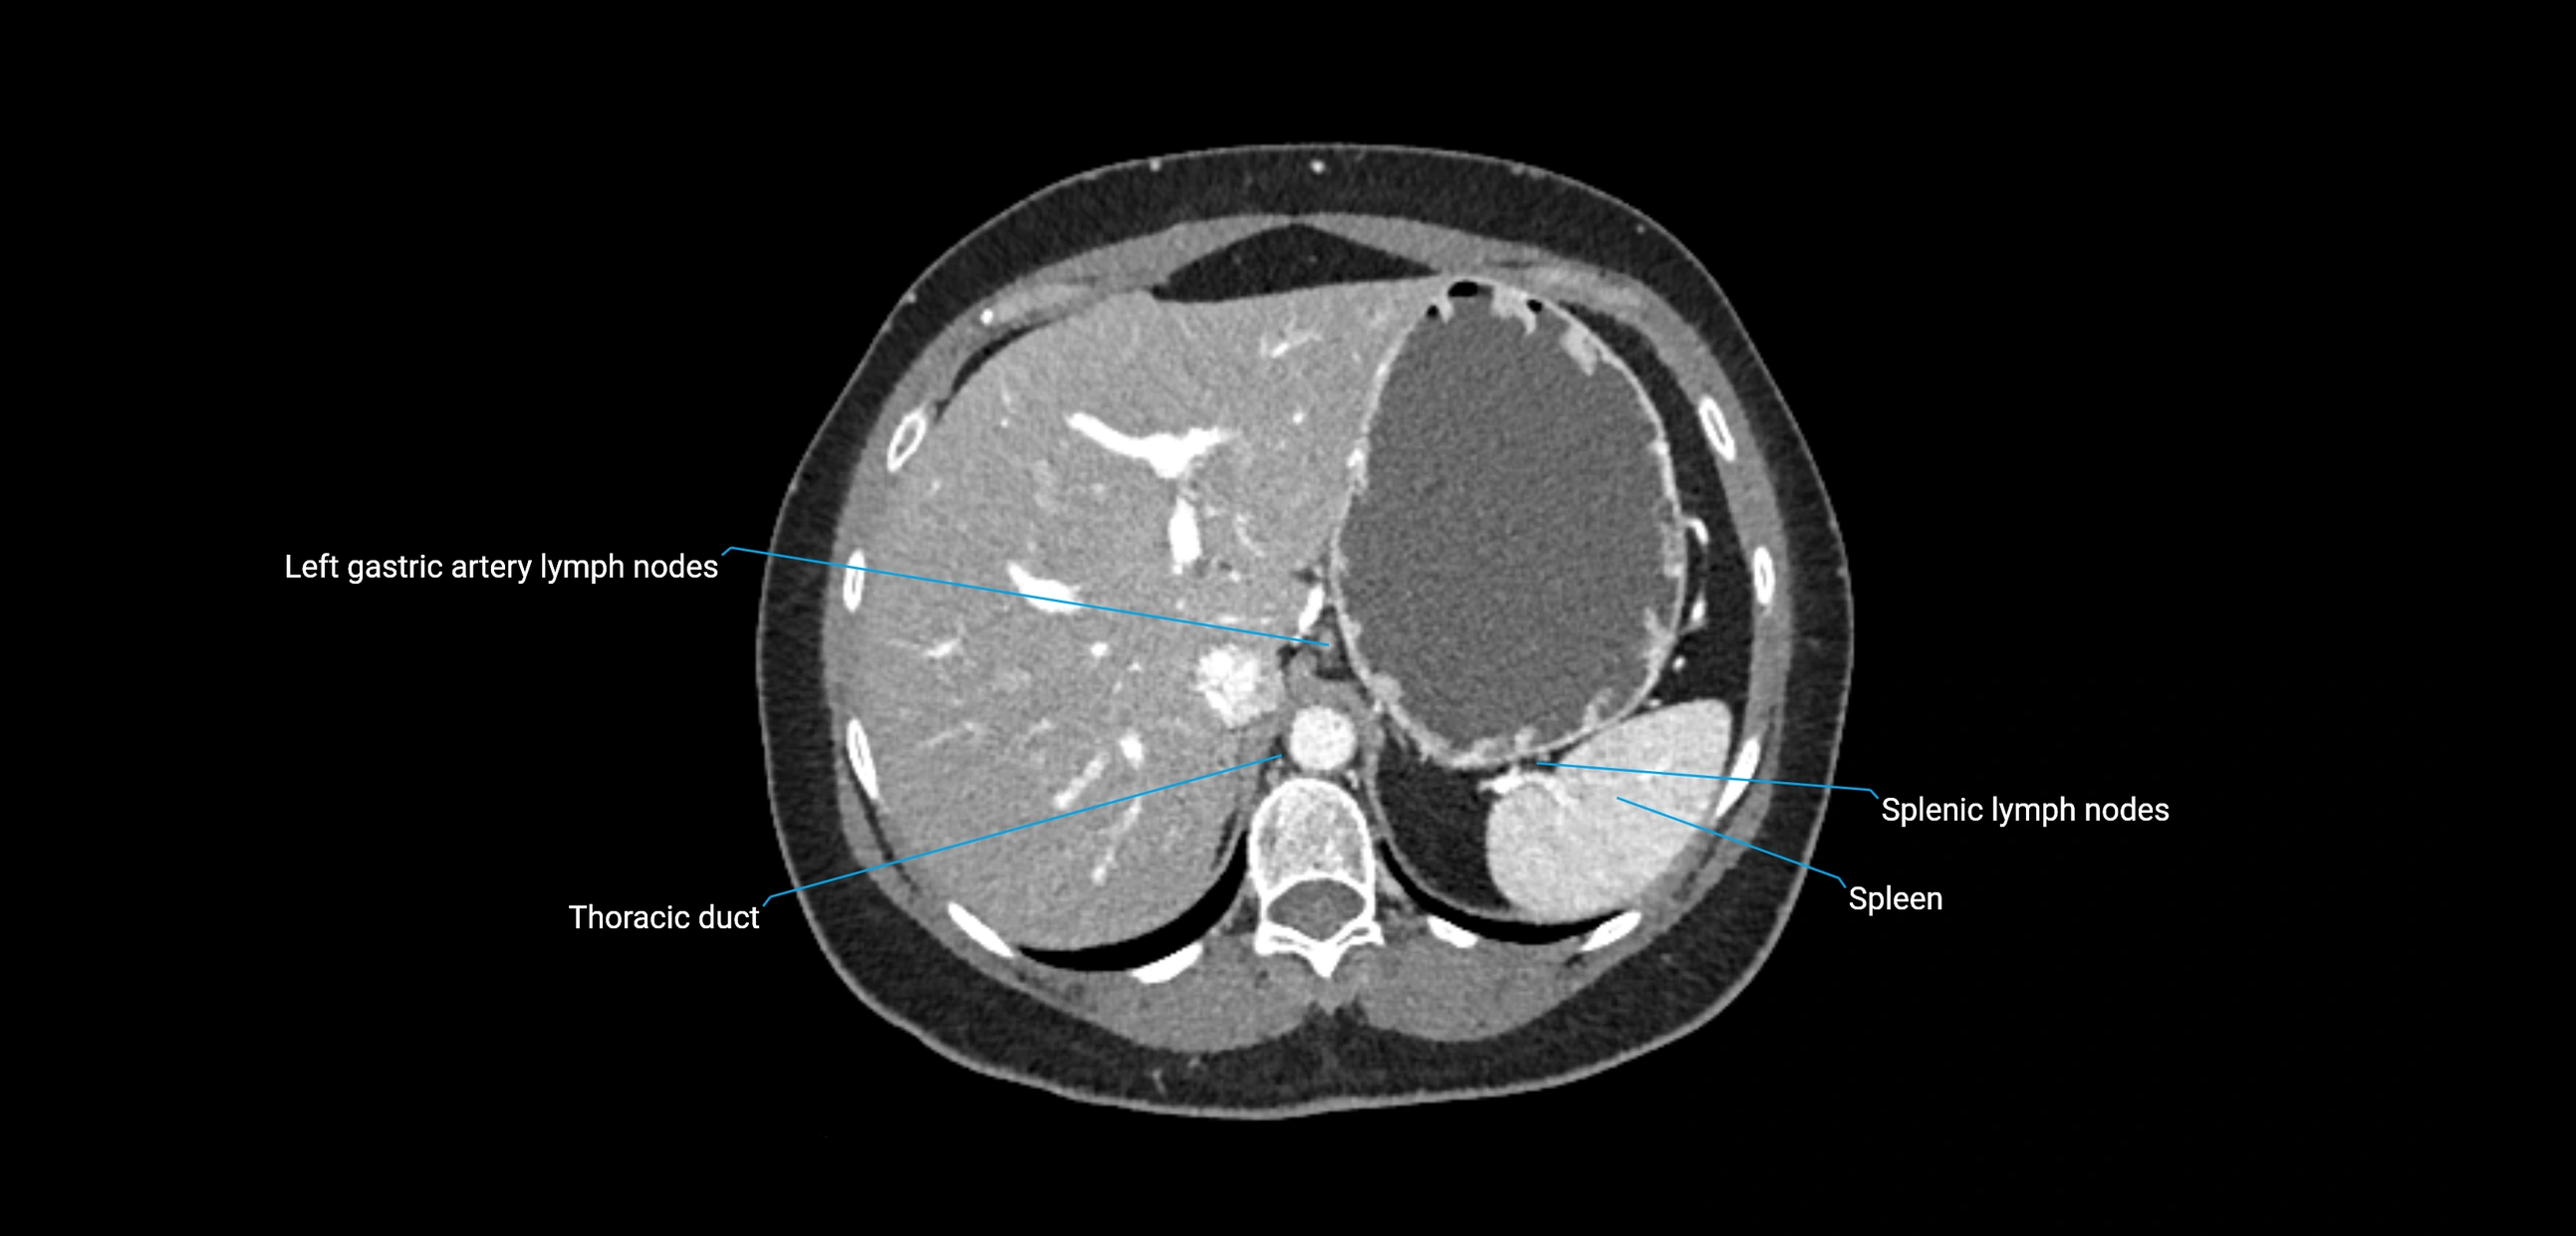

CT Appearance

CT Pre-Contrast:

• Nodes appear as soft-tissue density nodules adjacent to the aorta and IVC

• Calcification may be seen in chronic infections (e.g., tuberculosis)

CT Post-Contrast:

• Normal nodes enhance homogeneously

• Malignant nodes may show heterogeneous enhancement, central necrosis, or conglomerate formation

• Size >1 cm short axis is suspicious, though morphology and distribution are equally important

CT image

image